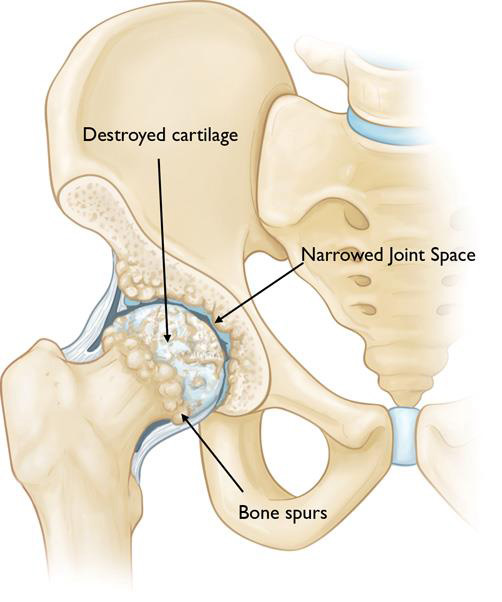

In hip osteoarthritis, the smooth articular cartilage wears away and becomes frayed and rough.